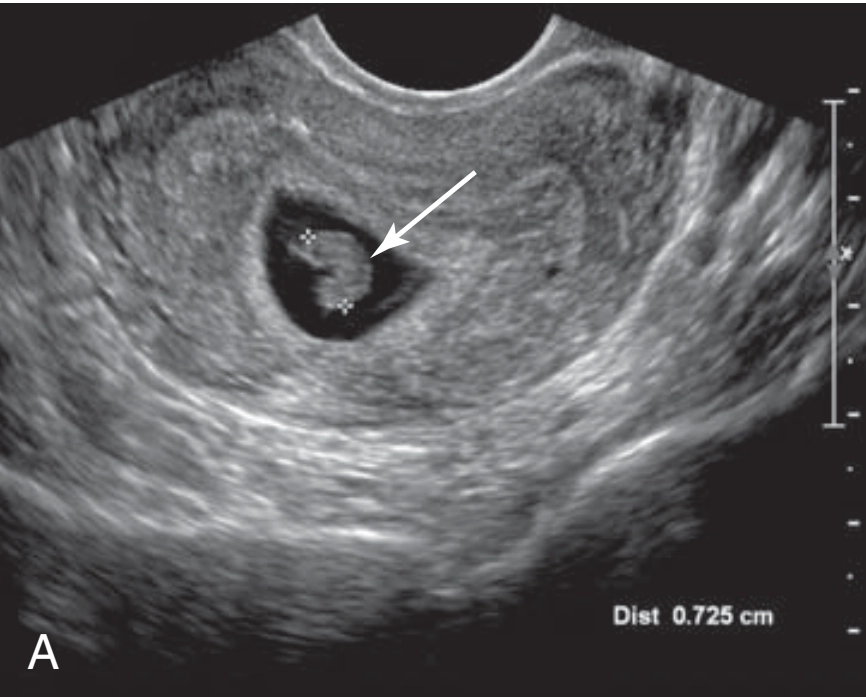

Chẩn đoán xác định sẩy thai